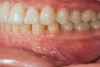

Fig 14.  Prosthetic phase completion. Left lateral view. Note vertical dimension change in posterior as evidenced by the buccal cusp tip position of tooth No. 12 versus papillary tissue of teeth Nos. 20 and 21 as compared to initial presentation (Fig 4).

Figure 14